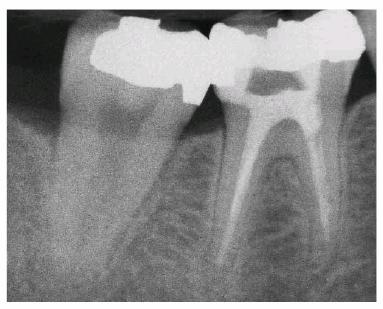

the amalgam-tooth interface (Figur 323s1823d es 18-12A 18-12B 18-12C 18-12D 18-12E, and 18-12F

Figur 323s1823d e 18-12A: Periapical radiograph showing tooth #30 after successful root canal treatment.

Figur 323s1823d e 18-12B: Bitewing radiograph showing tooth #30 with amalgam core build-up completed. Note that the core material extends approximately 2 mm into the canal orifices for increased retention.